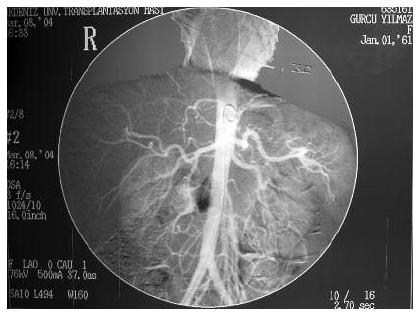

A 32-year-old woman with end-stage renal disease who had been maintained on hemodialysis owing to hypertensive nephrosclerosis and her 42-year-old sister as a haplo-identical donor were admitted to our center for a kidney transplant. During the donor evaluation, ultrasonographic examination of the kidneys revealed no abnormalities. Angiographic examination demonstrated what was believed to be a rotation abnormality of the left kidney (Figure 1).